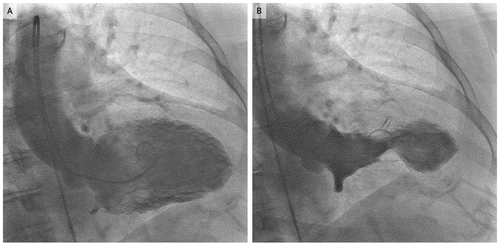

La experiencia de la mujer de 61 años, oriunda de Texas, es descrita en un nuevo estudio publicado en la revista New England Journal of Medicine, donde se señala que después de la muerte de Meha, su Yorkshire Terrier de 9 años, sufrió de cardiomiopatía Takotsubo, una condición más conocida como "síndrome de corazón roto".

La condición que sufrió Simpson replica los síntomas de un ataque cardíaco y se asocia con episodios traumáticos como la muerte de un familiar.